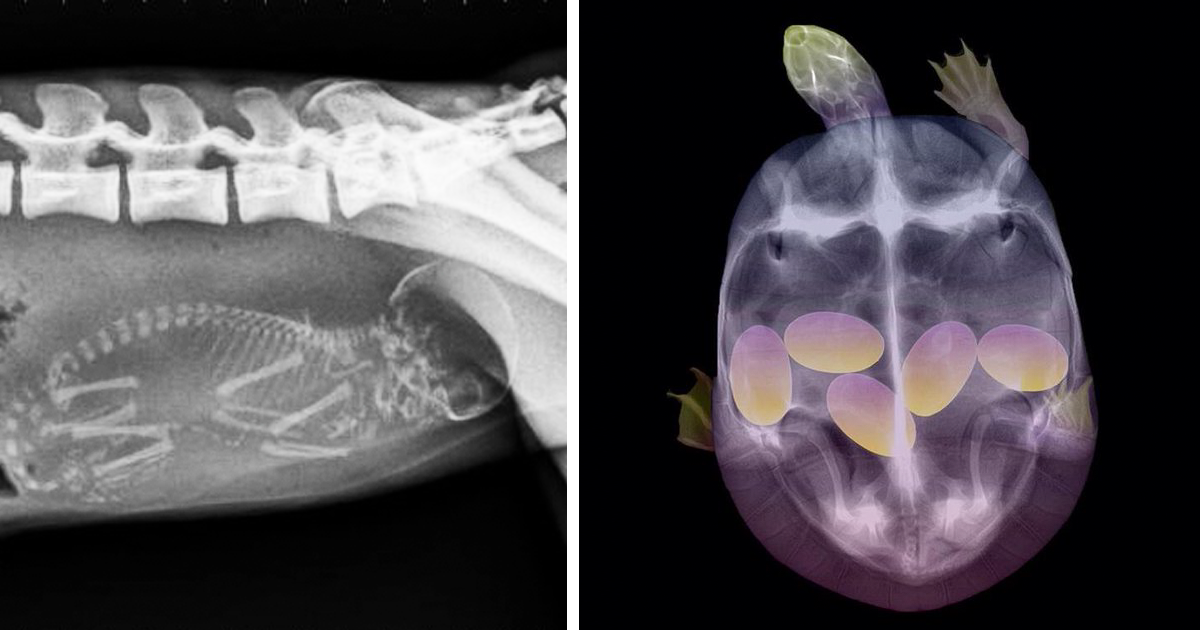

Грипп у беременной собаки - фото презентация